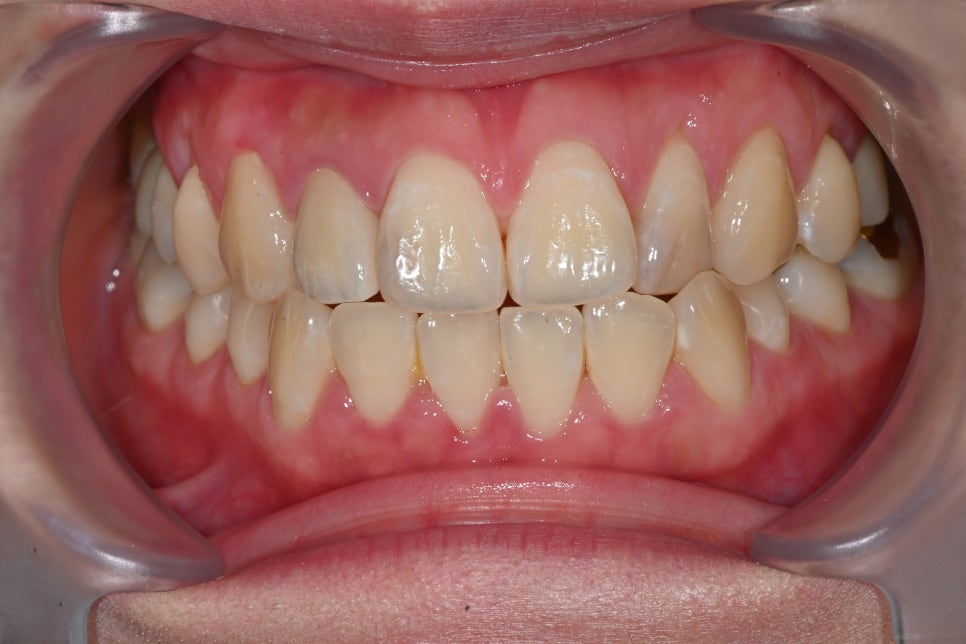

Changes after treatment

<BEFORE>

<AFTER>

Natural appearance of the gum line restored

A color harmony with the surrounding teeth

Improvement of the sense of incongruity in the front teeth

The response that it “looks like a natural tooth”

was especially impressive.